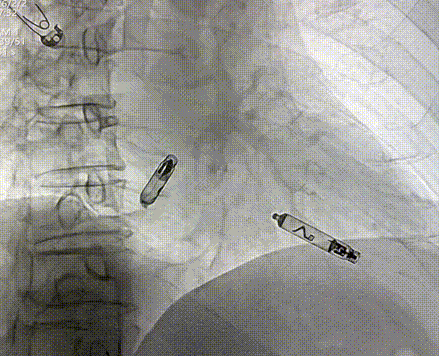

工程师进行定位标测(腔内图形、损伤、阻抗、感知、阈值),参数正常。在旋入固定之前,留存影像来记录机器“V形标记”的起始位置,缓慢顺时针旋转控制旋钮,旋入AVEIR™ AR器械过程中持续测试观察趋势,旋至1.5圈,进入对接栓模式;进行张力测试,整体轻微施加张力回撤导管,持续几个心动周期后将无导线起搏器返回松弛状态进行电学参数测试,参数稳定,完成心房无导线心脏起搏器植入。

体外对接心室无导线心脏起搏器,先将心室AVEIR™ VR推送至下腔静脉与右心房交界处,在血液中激活器械,体外搜索器械信号形成连接。在保护套筒覆盖下,操纵输送导管让AVEIR™ VR跨过三尖瓣,送入右心室,定位测试参数优秀, 术中可见损伤电流明显上升,提示起搏器与心肌接触良好。接着顺时针旋转控制旋钮,将起搏器旋入1.5圈后,进入对接栓模式,摇摆测试,见起搏器头端稳定,V型标志未转动,提示固定良好,完成心室无导线心脏起搏器植入。